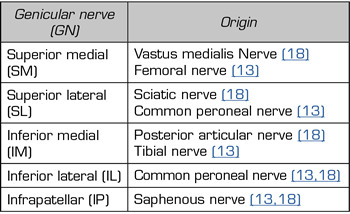

Although there is general agreement that the branches that innervate the knee joint capsule come from the femoral, sciatic, and obturator nerves, there is no consensus on the origin and number of branches innervating this area (Table I). To understand the innervation of the knee joint capsule, we divide it into two compartments: An anterior and a posterior (10). The innervation of the posterior articular capsule originates from the tibial nerve and the posterior division of the obturator nerve (11,12). The innervation of the anterior articular capsule (Figure 1) is divided into 4 quadrants (13,14): The lateral superior quadrant is innervated by the vastus lateralis nerves (VLN), vastus intermedius nerve (VIN, superior lateral genicular nerve (SLGN), and common peroneal nerve (CPN). The inferolateral quadrant receives innervation of the inferior lateral genicular (ILGN) and recurrent peroneal (RPN) nerves. The medial superior quadrant is innerved by the nerves of the vastus medialis (VMN), VIN, and superior medial genicular nerve (SMGN). The medial inferior quadrant receives innervation of the inferior medial genicular nerve (IMGN) and in some cases of the infrapatellar branch of the saphenous nerve (IPBSN).

Table I. Innervation of the anterior knee joint capsule